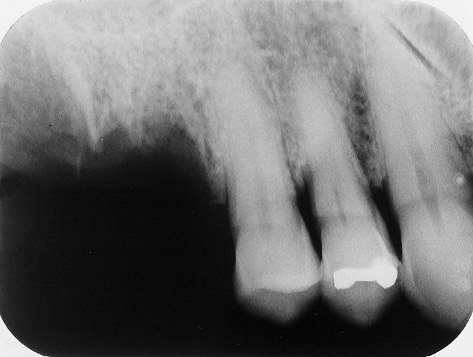

29. What condition can be seen on mesial surface of the tooth # 3.6?

30 / 30

30. What condition can be seen on mesial surface of the tooth # 3.4?